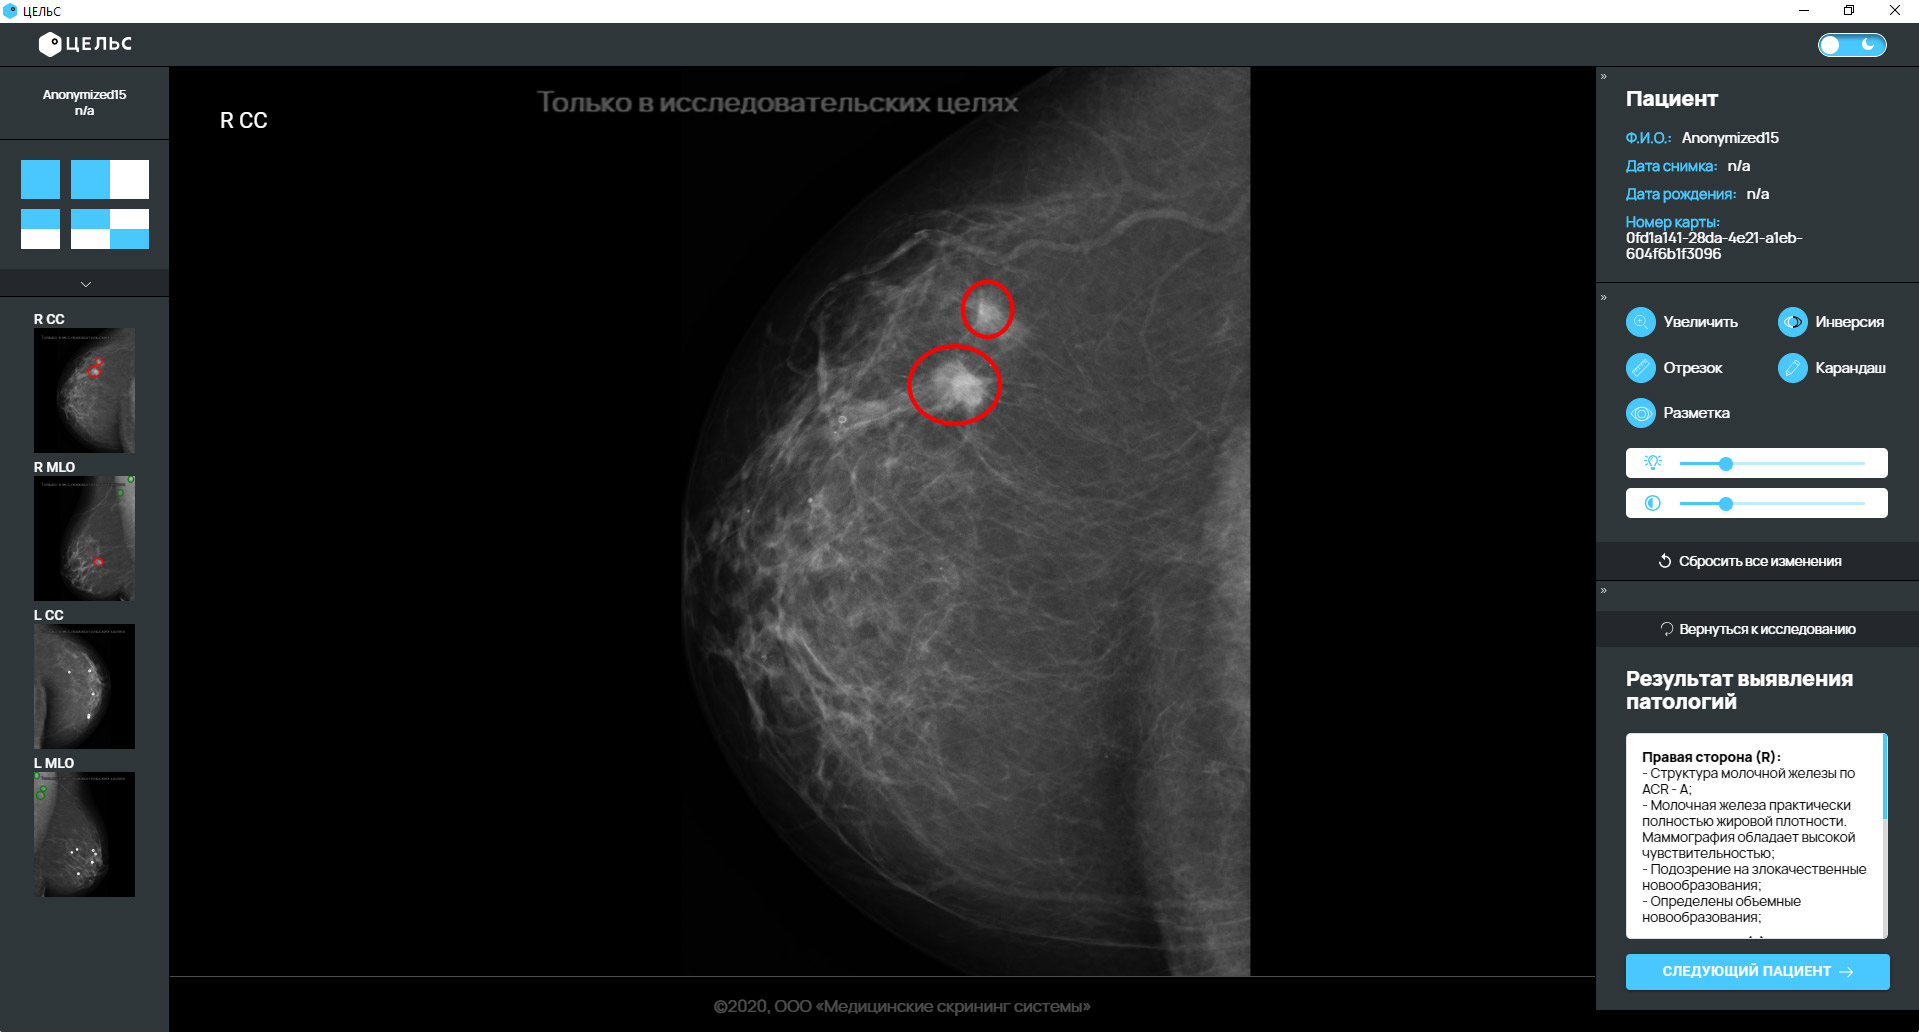

Без сомнения, искусственный интеллект (ИИ) Celsus сегодня является наиболее обсуждаемой темой в исследованиях медицинской визуализации, как в диагностических, так и в терапевтических. Только по диагностической визуализации количество публикаций по ИИ увеличилось примерно со 100–150 в год в 2007–2008 годах до 1000–1100 в год в 2017–2018 годах. Исследователи применили ИИ для автоматического распознавания сложных закономерностей в данных изображений и предоставления количественных оценок радиографических характеристик. В радиационной онкологии искусственный интеллект применяется к различным модальностям изображений, которые используются на разных этапах лечения. т.е.. определение опухоли и оценка лечения. Радиомика, извлечение большого количества элементов изображения из изображений с использованием излучения с использованием высокопроизводительного подхода, является сегодня одной из самых популярных тем исследований в области медицинских исследований изображений. Искусственный интеллект — это важная движущая сила обработки огромного количества медицинских изображений и, следовательно, выявляет характеристики заболевания, которые невозможно оценить невооруженным глазом. Цели этой статьи — проанализировать историю ИИ в исследованиях в области медицинской визуализации, его текущую роль, проблемы, которые необходимо решить, прежде чем ИИ сможет широко применяться в клинике, а также возможное будущее.